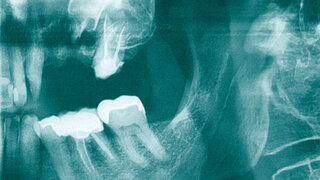

Mund-, Kiefer- und GesichtschirurgieDas ossifizierende Fibrom – ein seltener, gutartiger Knochentumor im Kieferbereich Dieser Fallbericht beschreibt den Befund eines ossifizierenden Fibroms im Unterkiefer, das mittels Enukleation therapiert wurde. Ausgabe 4/2023Chirurgie

MKG-ChirurgieFollikuläre Zyste in der Kieferhöhle infraorbital – mit Hypästhesie Bei einer Hypästhesie des Nervus infraorbitalis nV2 sind Überraschungen durchaus möglich, wie der Patientenfall zeigt. 29.01.2021 ZahnmedizinChirurgie

Zufallsbefund eines Riesenzelltumors bei langjähriger Bruxismus-Patientin 07.10.2020 ZahnmedizinChirurgie

MKG-ChirurgieÜberpresstes Provisorienmaterial als Ursache für eine Sinusitis maxillaris Mund-Antrum-Verbindungen (MAV) können bei jeder Extraktion im Oberkieferseitenzahnbereich entstehen. Im vorliegenden Fall wurde Provisorienmaterial über eine MAV in die Kieferhöhle überpresst. Ausgabe 17/2020ZahnmedizinChirurgie